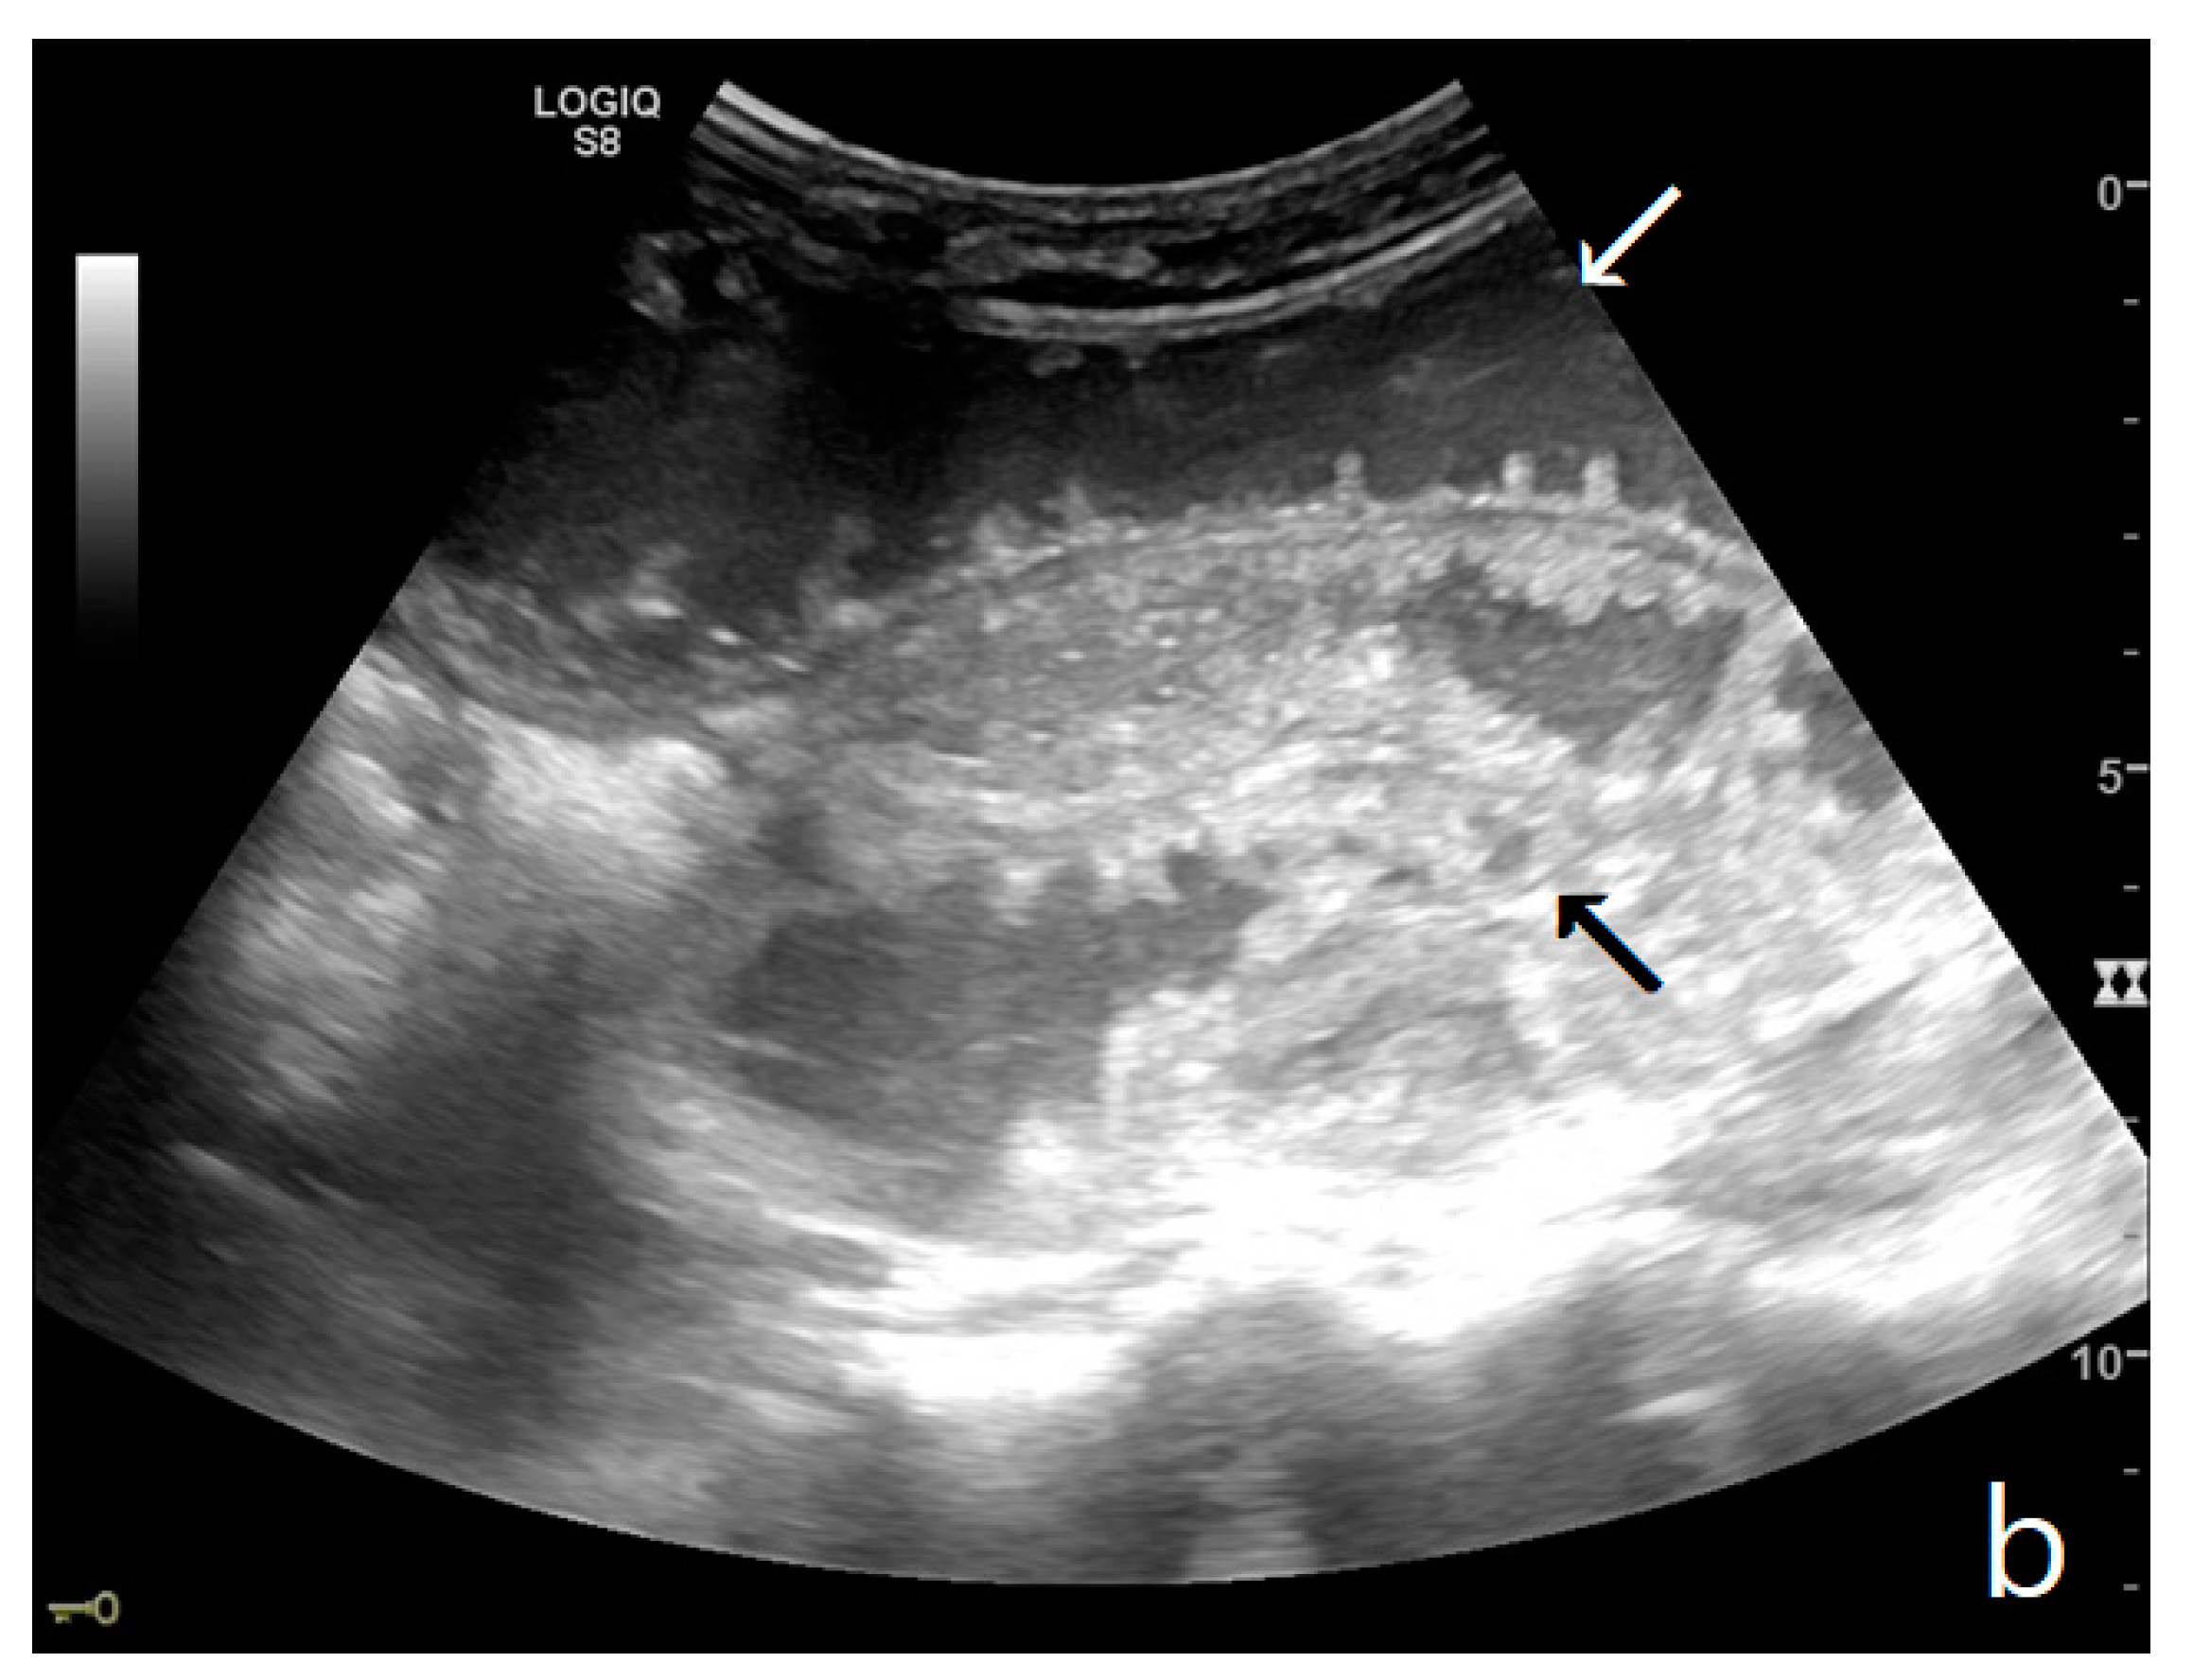

Figure 3.

A decompensated SBO, presenting fluid-filled, dilated small bowel loops with increased parietal thickening (*) (a) and free fluid between bowel loops (a). ‘Caliber jump’: a difference in caliber between the swollen loops upstream (white arrows) (a,b) and the collapsed loops downstream of the obstruction (black arrows) (a,b).